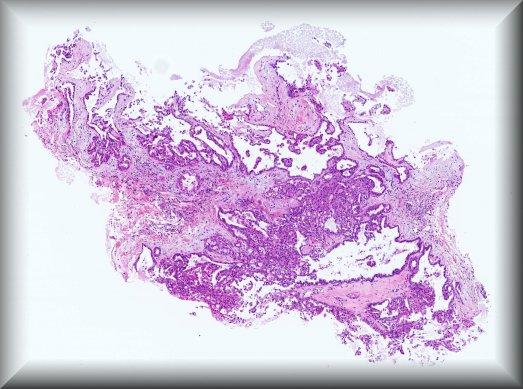

Jolique van Ipenburg (Nijmegen): 50-year-old male, retinoblastoma survivor, with conjunctival squamous lesion. Protocol |